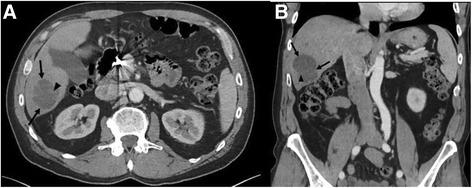

Here we describe the case of a 63-year-old man who presented initially with angiosarcoma of the nose and received surgery for the primary. Over 4 years he had recurrent disease in the face and liver and was treated with nab-paclitaxel, surgery, and radioembolization, but continued to have progressive disease. His tumor was found to express PD-L1 and he received off-label pembrolizumab 2 mg/kg every 21 days for 13 cycles with marked shrinkage of his liver disease and no new facial lesions. Secondary to this therapy he developed hepatitis and has been treated with decreasing doses of prednisone. During the 8 months off therapy he has developed no new or progressive lesions.